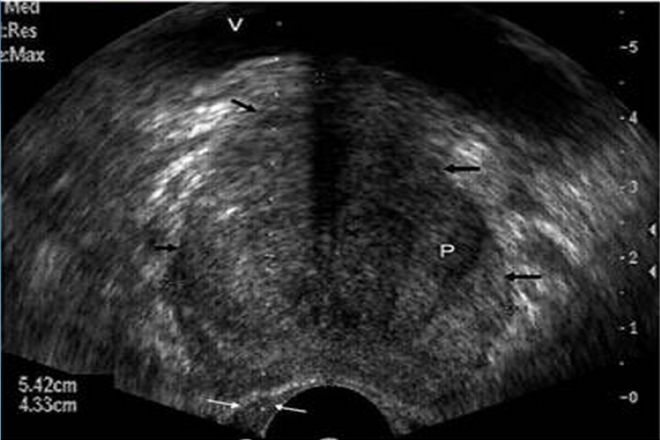

Subdivisiones funcionales del hígado.

Internamente, donde el parénquima hepático se muestra continuo existen dos hígados (porciones o lóbulos portales), son funcionalmente independientes: derecho e izquierdo. Cada porción tiene sus ramas primarias de la arteria hepática propia, de la vena porta hepática y su propio drenaje biliar. El lóbulo caudado